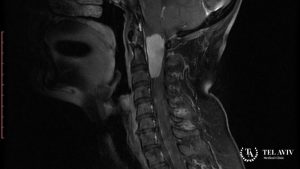

Для подтверждения наличия патологии, специалист применяет такие диагностические методы:

- КТ и МРТ.

Данные исследования помогают специалисту определить характер опухоли, ее форму, размер, локализацию, состояние соседних тканей и поставить точный диагноз. Дальнейшую тактику лечения врач разрабатывает индивидуально.